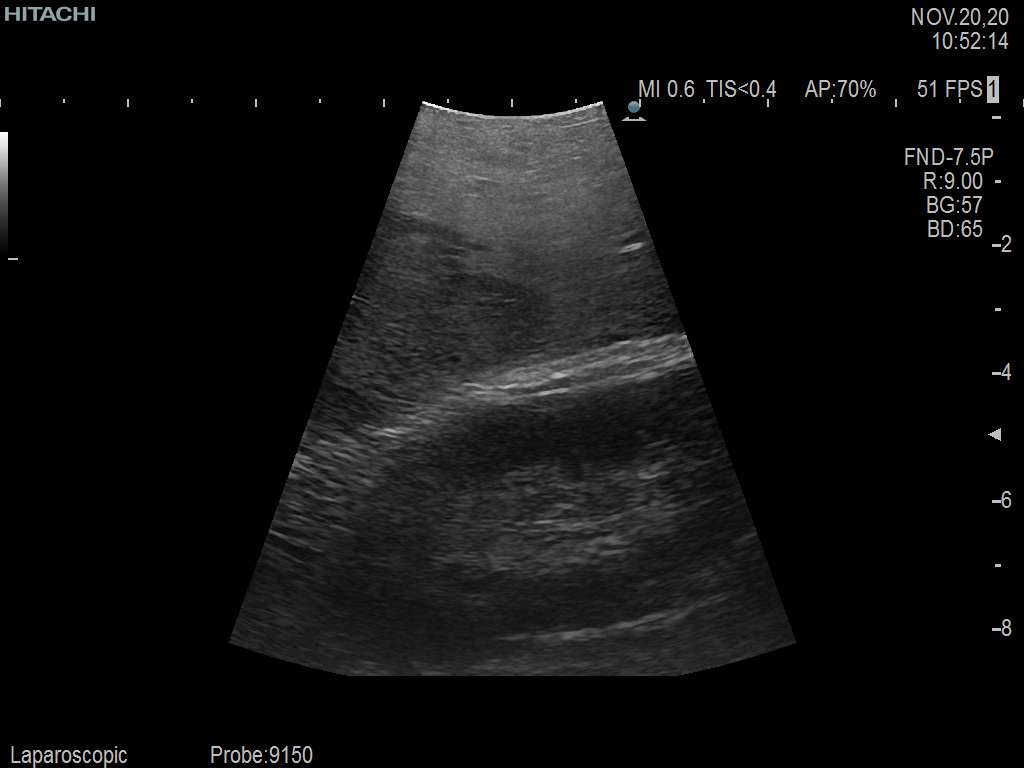

Laparoscopic Partial Nephrectomy & Hepatectomy using C9150LA

Curved array 4-way laparoscopic transducer for better visualization of targeted lesions, providing instant  feedback on tumor margin delineation.